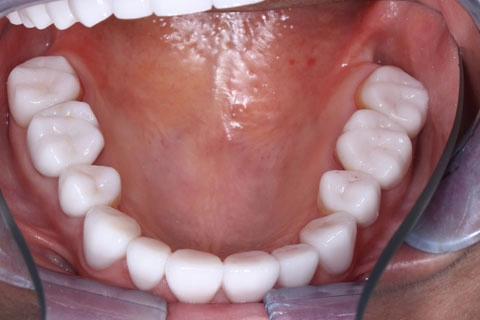

Проведена ортопедическая реабилитация.

Фронтальная группа зубов верхней и нижней челюстей – установлены виниры из литий дисиликата.

Жевательная группа – восстановлена коронками из диоксида циркония, в том числе 3.6, 4.6 – коронки на имплантатах.

Фронтальная группа зубов верхней и нижней челюстей – установлены виниры.

Жевательная группа – восстановлена коронками из диоксида циркония, в том числе 3.5, 4.5 – коронки на имплантатах.